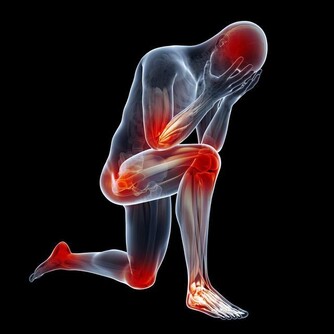

*****9.高膽固醇血症有時可能會表現在皮膚上。*****

有些血清總膽固醇高的人,會在眼皮、關節、雙手或身體其他部位長出黃中帶紅的腫塊(醫學上被稱為黃色瘤)。此外,糖尿病患者和患有家族性高膽固醇血症這種遺傳病的人也有可能長黃色瘤。醫生建議人們從20歲起每3年檢查一次,或者根據醫生的建議更為頻繁地檢查。